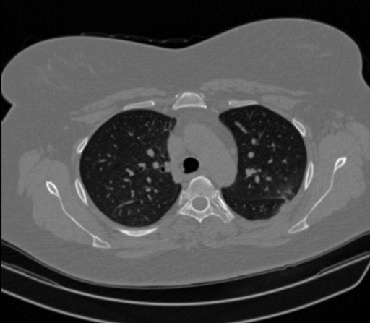

It should be mentioned that for explainability purposes [7, 8, 9], an anchor set was generated for the COV19-CT-DB database [5]. This included 11 anchors, each representing a respective 3-D CT scan obtained through an appropriate clustering procedure. Figure 2 shows a series of slices from a COVID-19 case, whereas Figure 3 shows a series of slices from a non COVID-19 case.